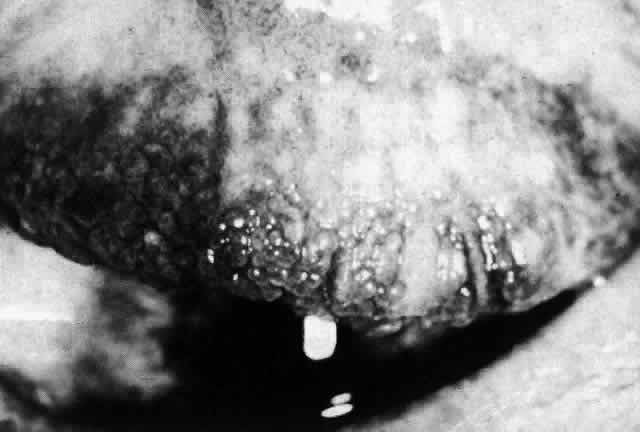

The eye may be affected in toxic epidermal necrolysis (Figs. 8 and 9). A mucopurulent conjunctivitis is the most common lesion, but symblepharon, eyelid changes, and corneal complications may develop in severe cases. Other causes include viruses, malignancies, graft-versus-host disease, and vaccines.32

Fig. 8. Extensive “burnlike” skin lesions in toxic epidermal necrolysis. (Courtesy of Dr. HB Ostler)

Fig. 9. Eyelid involvement in toxic epidermal necrolysis. (Courtesy of Dr. HB Ostler)